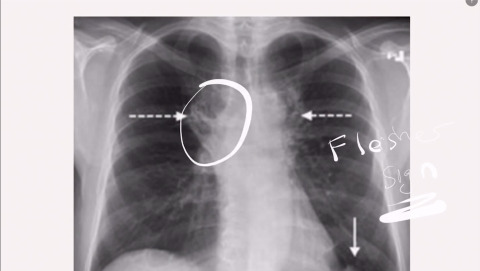

Chest X-ray in Pulmonary Embolism

Mel Herbert reviews the key chest x-ray findings in a patient with a PE.